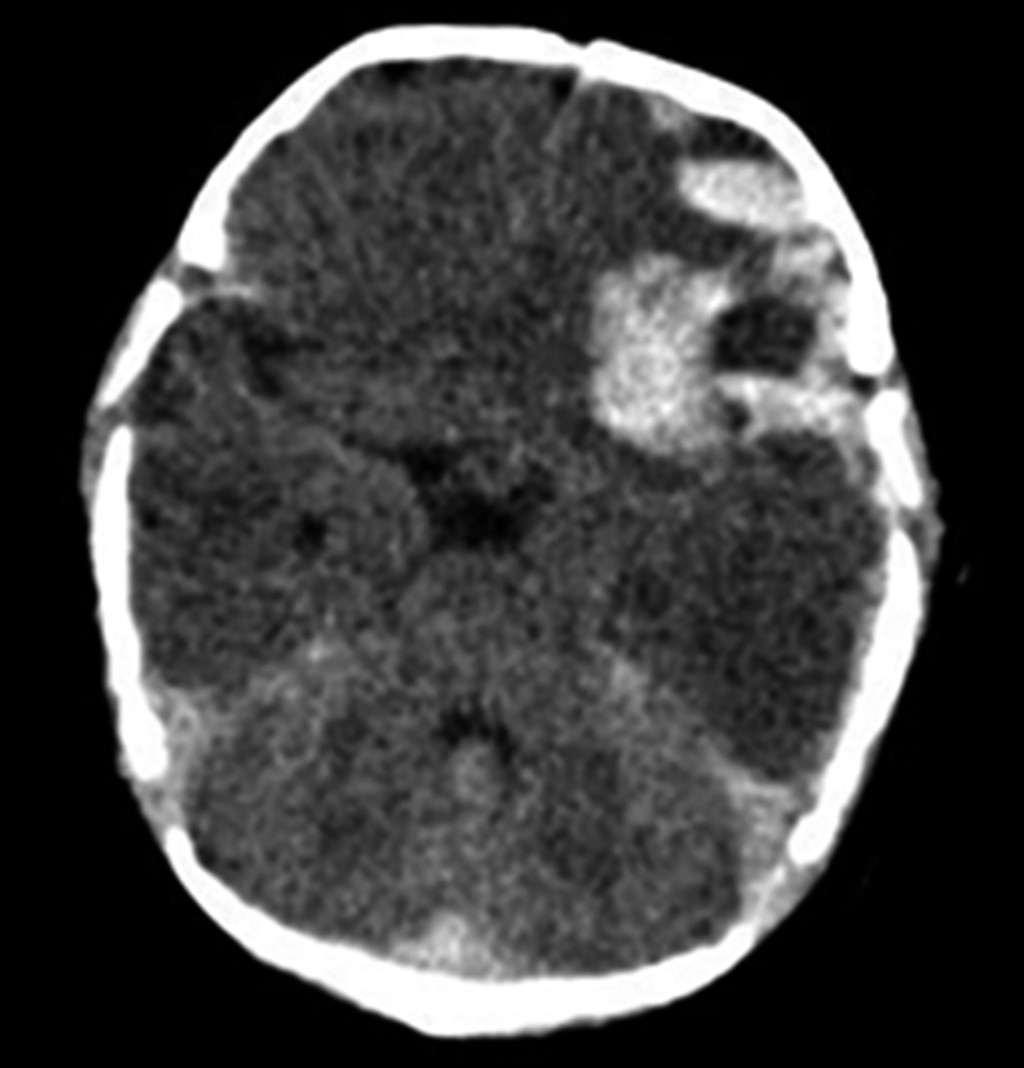

Late hemorrhagic disease of the newborn

Introduction: hemorrhagic disease of the newborn can be prevented with prophylactic administration of vitamin K. Case presentation: 33-day-old female patient, without prenatal control, home delivery, and without administration of vitamin K prophylaxis. Her condition was characterized by a clinical picture of intracranial hypertension, in addition, in laboratory tests, prolonged coagulation times and elevated D-dimer were documented. Late hemorrhagic disease of the newborn was diagnosed with subdural hematoma. Treatment consisted of administration of vitamin K, fresh frozen plasma, and surgery. In the short and medium term, her evolution was satisfactory, without neurological sequelae. Conclusion: vitamin K deficiency hemorrhagic disease can occur up to two months of life; in cases where prophylaxis is not given, its identification is important to prevent serious complications.

Figure 1